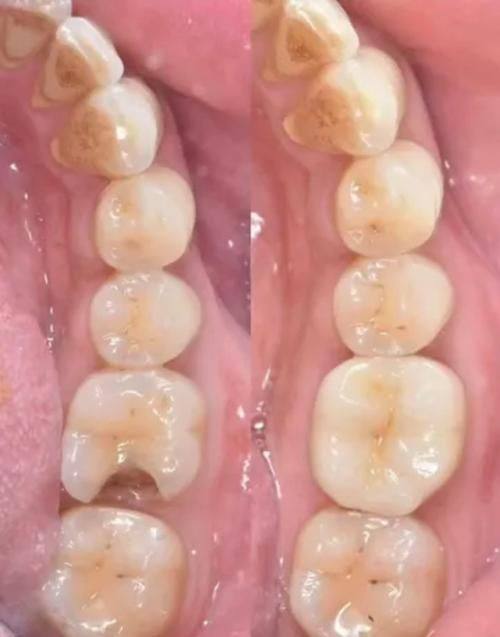

3. 王茜:曾在湘雅口院工作,师从吴颖芳及刘迎春医生,擅长嵌体、全瓷牙、根管治疗、牙周刮治、青少年口腔综合诊疗。

13. 根管治疗:500 - 1500元/根